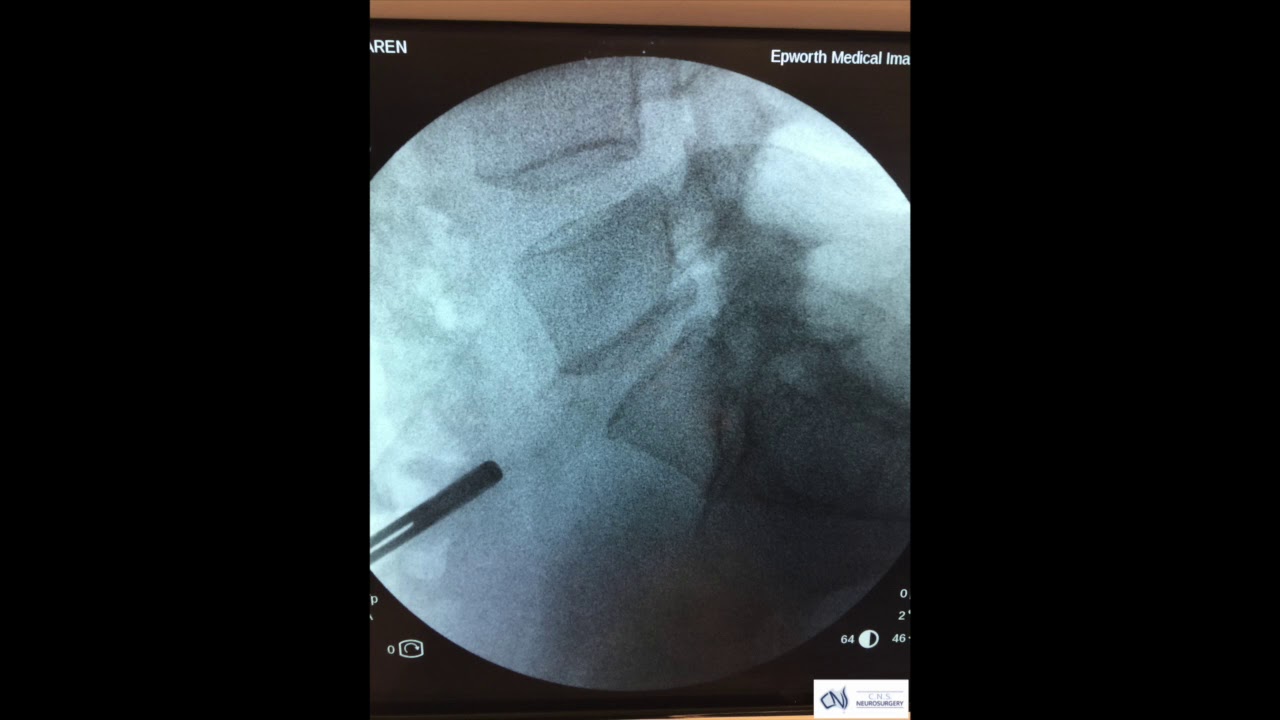

Lumbar spine anteroposterior and lateral Xray views showing optimal What Is Lumbar Arthroplasty See diagnosing lumbar degenerative disc disease Disk replacements can be performed in the cervical and lumbar spine and, if necessary, several replacements can be done in one operative procedure. Recovery typically takes two to six weeks, and. Artificial disc replacement is recommended for lumbar degenerative disc disease that has been confirmed through a rigorous diagnostic process, including identification on an. What Is Lumbar Arthroplasty.

From www.youtube.com

Lumbar Disc Arthroplasty YouTube What Is Lumbar Arthroplasty Lumbar disc replacement (ldr) or arthroplasty involves removal of the diseased disc and replacement with an artificial mechanical one. See diagnosing lumbar degenerative disc disease Artificial disc replacement is recommended for lumbar degenerative disc disease that has been confirmed through a rigorous diagnostic process, including identification on an imaging scan. In this review we present an overview of lumbar disc. What Is Lumbar Arthroplasty.